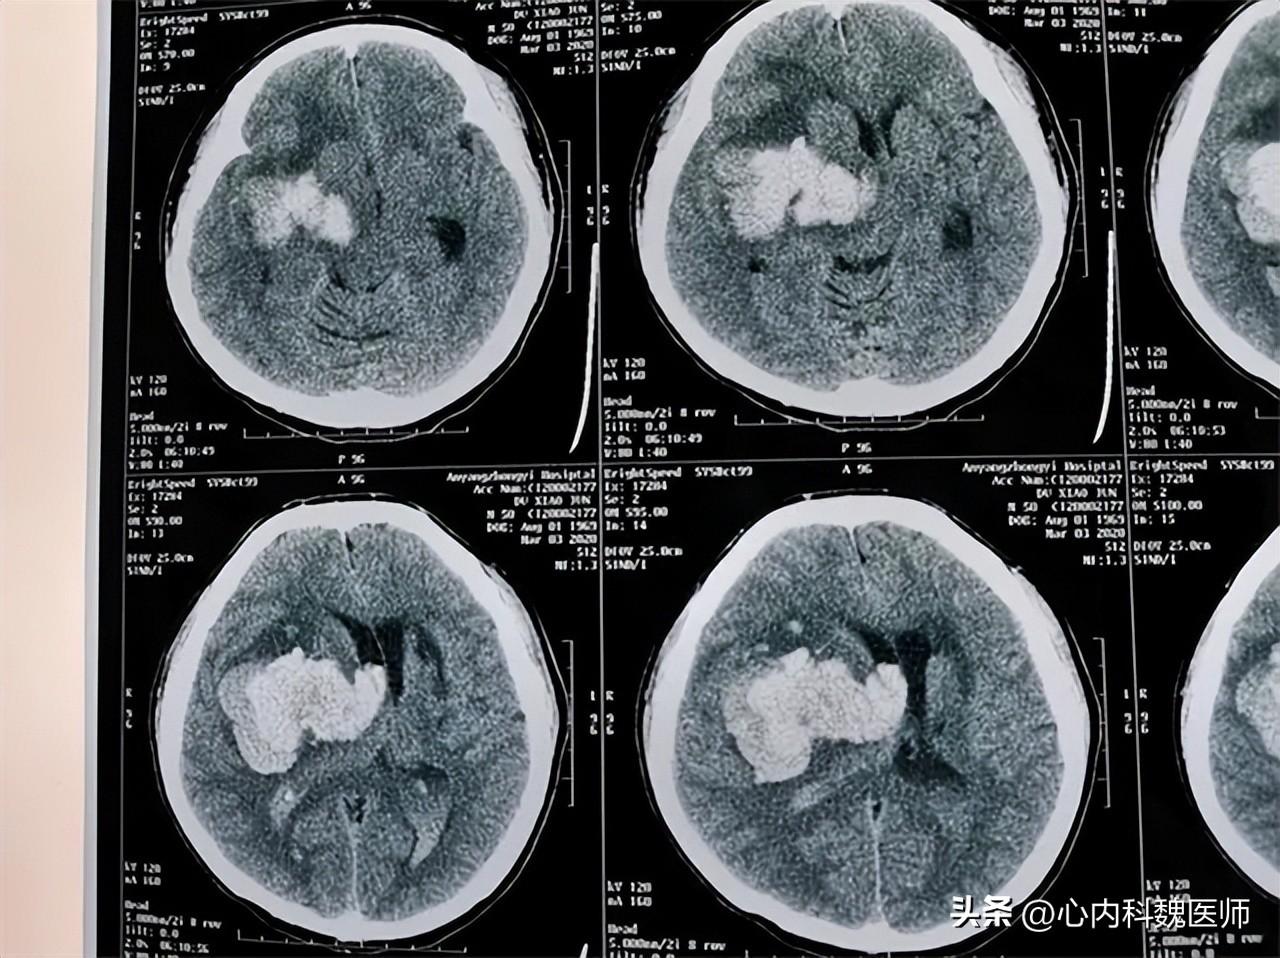

(在此處可以附上一些與頭部創(chuàng)傷相關(guān)的圖片、表格等輔助材料,以便讀者更好地理解和記憶。)